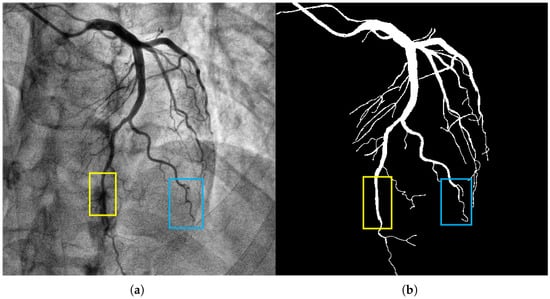

The coronary vessels (especially the aortic segment) present a distinct tubular morphology characterized by thinness, length, continuity, and directional consistency (as shown in the yellow box in Figure 1). The tubular morphology of coronary vessels has the following differences: (1) The diameter of blood vessels shows a uniform change trend with the increase in branching levels. The diameter of the main trunk can reach 2–3 mm, while that of the terminal branches is only 0.2–0.3 mm. (2) The gray value of the blood vessel wall shows a gradient change, which is prone to being confused with background artifacts. The above characteristics require the segmentation model to have strong capabilities in extracting tubular features and adapting to different scales. It must accurately capture the main vessels while avoiding missing the delicate branches.

Figure 1.

The image in panel (a) presents a coronary artery angiogram depicting the vascular structure, which includes both the main and fine branches. The yellow box highlights the aortic segment, and the blue box indicates a branch with complex morphology. The segmentation target in panel (b) captures the coronary vessels with the mask annotations clearly delineating the vascular structures. The background artifacts, including overlapping tissues and bones, were handled effectively by our model, reducing false positive detections. Methodologically, the CFEM played a key role in enhancing the extraction of tubular features, especially in the fine branches, across varying vessel scales.

Coronary vessels have a tree-like topological structure. The distal end of the aorta can be divided into the left anterior descending branch, the left circumflex branch, the right coronary artery, etc., as the main branches, and each branch is further divided into multiple levels of fine branches (as shown in Figure 1, the blue box). The projection characteristics of two-dimensional DSA images cause the superimposition of different depths of vascular branches, which alters the uniform change trend of vascular diameters and increases the difficulty of segmentation [18,19,20,21,22]. Moreover, areas with vascular intersections and bends are prone to sudden drops in gray values, making it difficult for traditional models to maintain segmentation connectivity. Therefore, a specially designed long-distance dependent modeling module is required to restore the dendritic structure of the blood vessels.